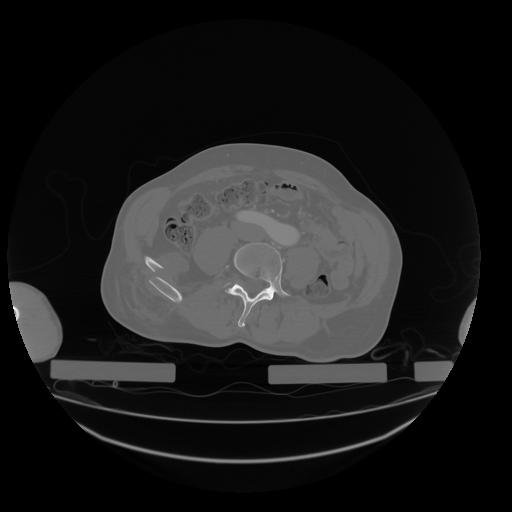

28 CUERPO,CE,Vol,2.0,CUERPO,,